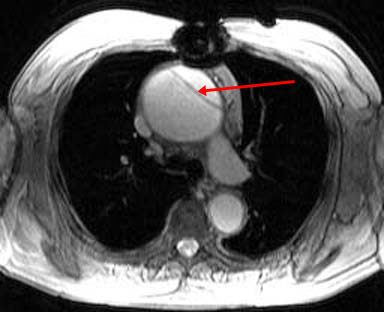

Answer: D. Stanford Type A Aortic Dissection. This image shows a dilation of the ascending aorta with a normal caliber descending aorta. An intimal flap can clearly be seen in the ascending aorta (arrow) representing an aortic dissection. There is no wall thicken to suggest an intramural hematoma. This aortic dissection is Stanford Type A since it includes the ascending aorta; Type B would include only the descending aorta. Somner T, Freshke W, Holzknecht N et al. Aortic dissection: a comparitive study of diagnosis with spiral CT, multiplanar transesophageal echocardiography, and MR imaging. Radiology 1996; 199(2): 347-52.17) What abnormality is seen on the T1-weighted (left) and T2-weighted (right) images below? ![]() Answer: A. Pericardial Cyst. These images show a homogenous mass (arrowheads) in the right cardiophrenic angle that is adherent to the pericardium and has relatively high signal on T2-weighted images and relatively low signal on T1-weighted images. The signal characteristics and cardiophrenic location are classic for a pericardial cyst. A lipoma would have signal characteristics that mirror subcuanteous fat. A myxoma would be within the heart itself. A pericardial mesothelioma would be more heterogenous. Constrictive pericarditis normally appears as a thickening of the pericardium, but these images clearly show a mass. Breen, JF. Imaging of the Pericardium. Journal of Thoracic Imaging 2001; 16(1): 47-54.18) This image is most consistent with what diagnosis? ![]() Answer: C. Amyloidosis. This image shows DHE sparing the subendocardium in a somewhat patchy distribution (arrows); this is most consistent with amyloidosis. There is no pericardial thickening to suggest constrictive pericarditis. Transmural and subendocardial infarctions would have DHE in a coronary artery distribution. VSD would demonstrate a connection between the ventricles. Maceira AM, Fisher NG, McKenna WJ, Pennell DK, et al. Cardiovascular magnetic resonance in cardiac amyloidosis. Circulation 2005; 111(2): 186-93.19) What abnormality is seen in the sagital view below? ![]() Answer: C. Aneurysm of the aortic root. This image shows a fusiform aneurysm of the aortic root (arrows) in a patient with Marfan�s syndrome. Additionally, there is loss of the distinctness of the sinotubular junction (arrowheads), a common finding in patients with Marfan's syndrome. Compare with the normal aorta in the image to the right (coronal image). These patients need periodic examinations to determine the necessity of prophylactic surgery to prevent aortic dissection. There is no intimal flap seen, so the patient has not yet suffered a dissection. Fattori R, Bacchi Reggiani L, Pepe G, Napoli G, Bna C, Celletti F, Lovato L, Gavelli G. Magnetic resonance imaging evaluation of aortic elastic properties as early expression of Marfan syndrome. Journal of Cardiovascular Magnetic Resonance 2000; 2(4): 251-6.20) What abnormality is seen in the DHE image below? ![]() Answer: C. Microvascular obstruction. There is a focus of unenhanced subendocardium (arrow) surrounded by transmural DHE in the anteroseptum. This unenhanced subendocardium represents an area of microvascular obstruction (MO) within a transmural infarction. Gadolinium contrast media cannot enter an area of MO because the vessels are destroyed. Wu KC, Kim RJ, Bluemke DA, et al. Quantification and time course of microvascular obstruction by contrast-enhanced echocardiography and magnetic resonance imaging following acute myocardial infarction and reperfusion. Journal of American College of Cardiology 1998; 32:1756-1764. |